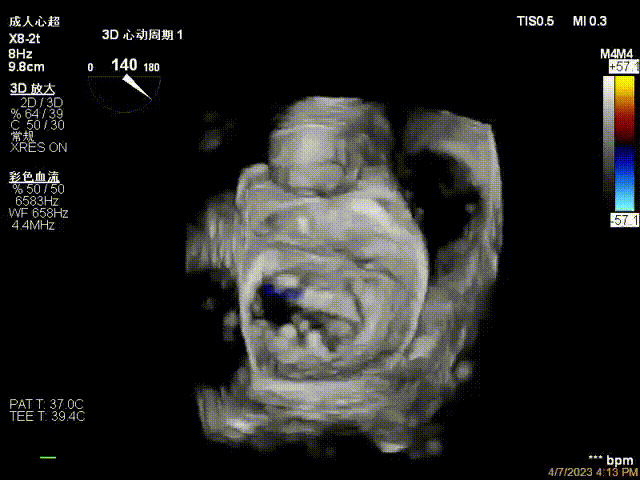

接受治療的是一例器質(zhì)性重度二尖瓣反流(DMR)患者,主訴“反復(fù)活動后胸悶,氣促3年余”。術(shù)前超聲顯示,雙房增大,二尖瓣脫垂伴重度反流,輕度三尖瓣反流,輕度肺高壓,升主動脈增寬。手術(shù)經(jīng)股靜脈-房間隔入路,采用全身麻醉插管,在TEE和DSA引導(dǎo)下完成房間隔穿刺。置入JensClip瓣膜夾系統(tǒng)后,在左房調(diào)整瓣膜夾的位置和軸向,后進入左室,在TEE引導(dǎo)下捕捉二尖瓣前后瓣葉,并關(guān)閉瓣膜夾。經(jīng)TEE反復(fù)確認手術(shù)效果后最終鎖定并釋放瓣膜夾。術(shù)后即刻超聲顯示瓣膜夾位置穩(wěn)定,功能良好,術(shù)前二尖瓣反流4+,術(shù)后0反流,肺靜脈逆流和左房壓都顯著好轉(zhuǎn),手術(shù)圓滿成功(以上數(shù)據(jù)都來源于醫(yī)院的臨床記錄)。術(shù)后患者狀態(tài)良好,目前已安排出院。

術(shù)后超聲顯示二尖瓣反流消失,瓣膜夾穩(wěn)定